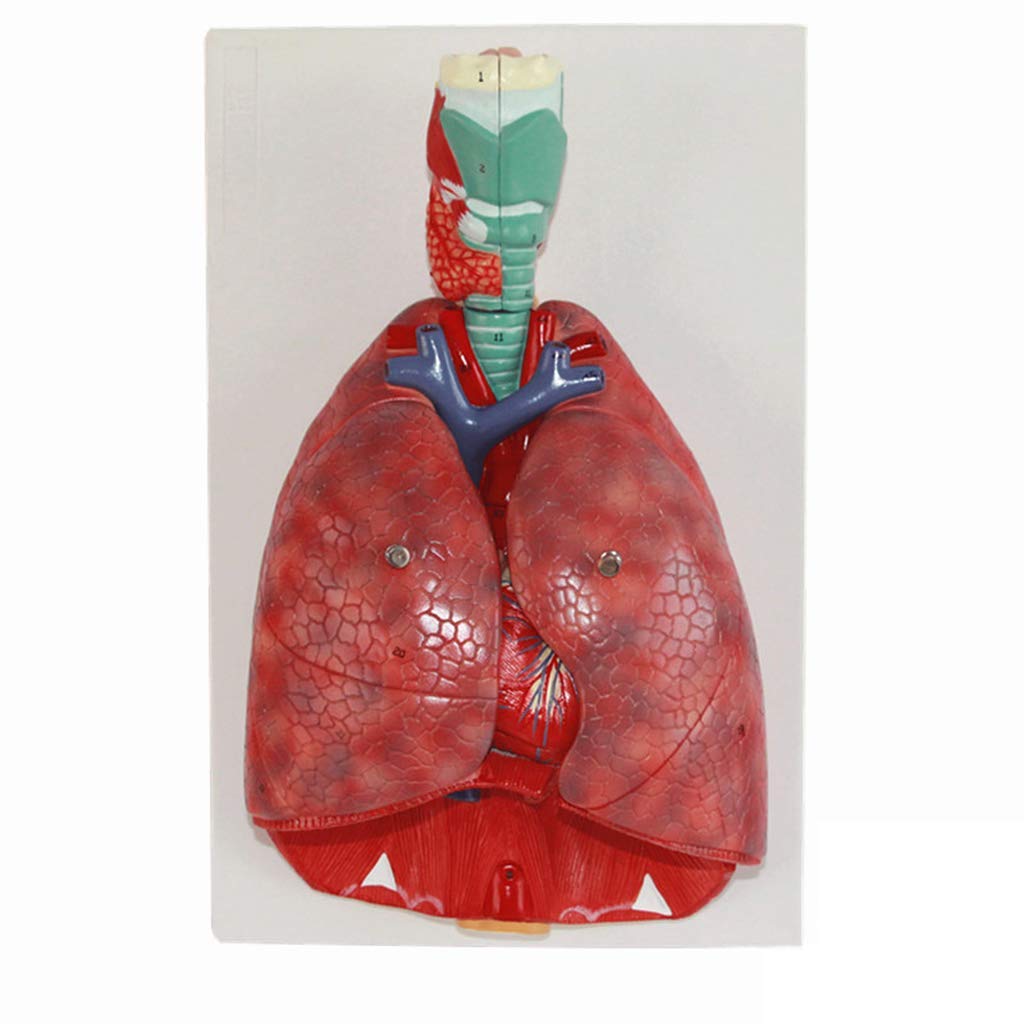

Anatomie Modell Vorlage VEVOR Menschliches Ohr Anatomie 3D-Modell, 3 Teile 5 Mal Vergrößertes Anatomie Modell Kostenlos ZAPION Torso- und Skelettmodelle Anatomisches, menschliches Alveolar Anatomische Larynx Herz Throat Lung Modell: Dieses Modell ist ein detailliertes, 7,1 x 5,9 x 7,5 Zoll (18cm x 15cm x 19cm) lebensgroße Modell Anatomie Herz Hals Lunge, die auf das Diagramm anatomisch genaue Merkmale mit entsprechenden Zahlen zeigt ., ., Lehrmittel: Verschiedene Farben werden verwendet, um verschiedene Positionen zu unterscheiden, und die Farben sind hell und leicht Studenten zu gewinnen Aufmerksamkeit, so dass Sie Lehre Demonstration zu können, die Studenten fördert das Verständnis und erhöht das Klassenzimmer fu. Genug jemand Interesse an dem Organ des Menschen zu befriedigen. Der Leistungsdruck stehen ist ein weiterer extrem wichtiger Indikator. Material: Es ist aus Lebensmittelqualität PVC umweltfreundlichen Materialien, hochwertige Prototypen, Handmade in einem festen, nicht gebrochen. ★ Da es sich um eine manuelle Messung ist, hat die Produktgröße einen kleinen Bereich Fehler finden Sie in dem eigentlichen Produkt, bitte verstehen. Cartoon-symbol für vollen magen anatomie des menschlichen organs... Anatomisches Modell von Nasenhöhle, Rachen, Lunge, 3D-Modell der Organe des menschlichen Atmungssystems mit farbiger Produkthandbuchkarte für medizinische Ausbildung und Training PVC ANATOMISCHES MODELL Der Leber Menschliches Normales Lebermodell - EUR 38,84.ZU VERKAUFEN! 386559494147 Es ist auch als Kommunikationsmittel für Ärzte und Patienten.